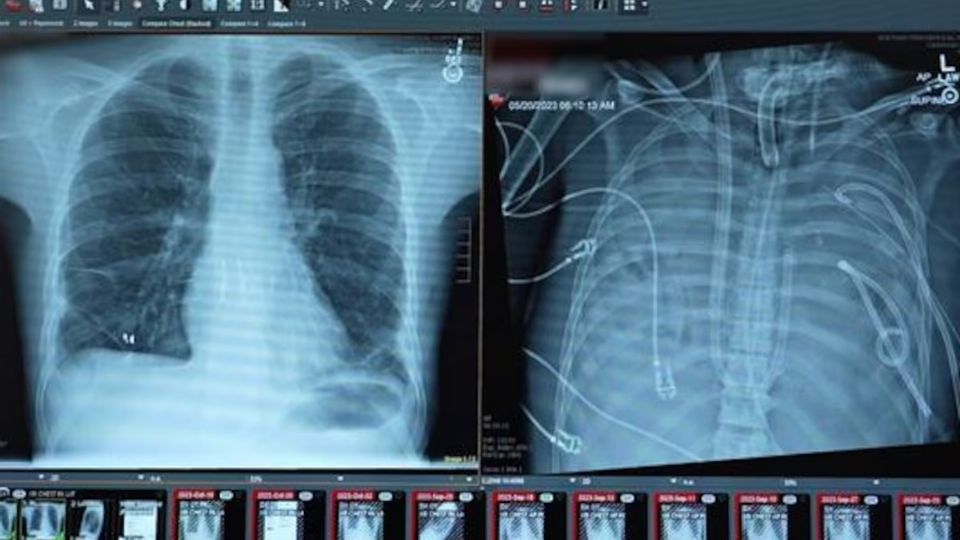

Un hombre de 33 años logró sobrevivir 48 horas sin pulmones gracias a un “pulmón artificial” desarrollado en el hospital Northwestern Medicine. El paciente permaneció conectado al sistema hasta recibir un trasplante doble de pulmón, un procedimiento pionero publicado en la revista científica Med.

Ante la gravedad del caso, el equipo médico decidió extirpar ambos pulmones y conectar al paciente a un sistema de "pulmón artificial" diseñado por el hospital.

Esta tecnología, denominada “sistema total de pulmón artificial extracorpóreo adaptado al flujo”, oxigena la sangre, elimina dióxido de carbono, y mantiene la circulación sanguínea estable, permitiendo que el corazón siga funcionando normalmente.

Permaneció 48 horas sin pulmones, con el tórax vacío, conectado únicamente al pulmón artificial bajo monitoreo constante, hasta recibir el trasplante doble de pulmón.